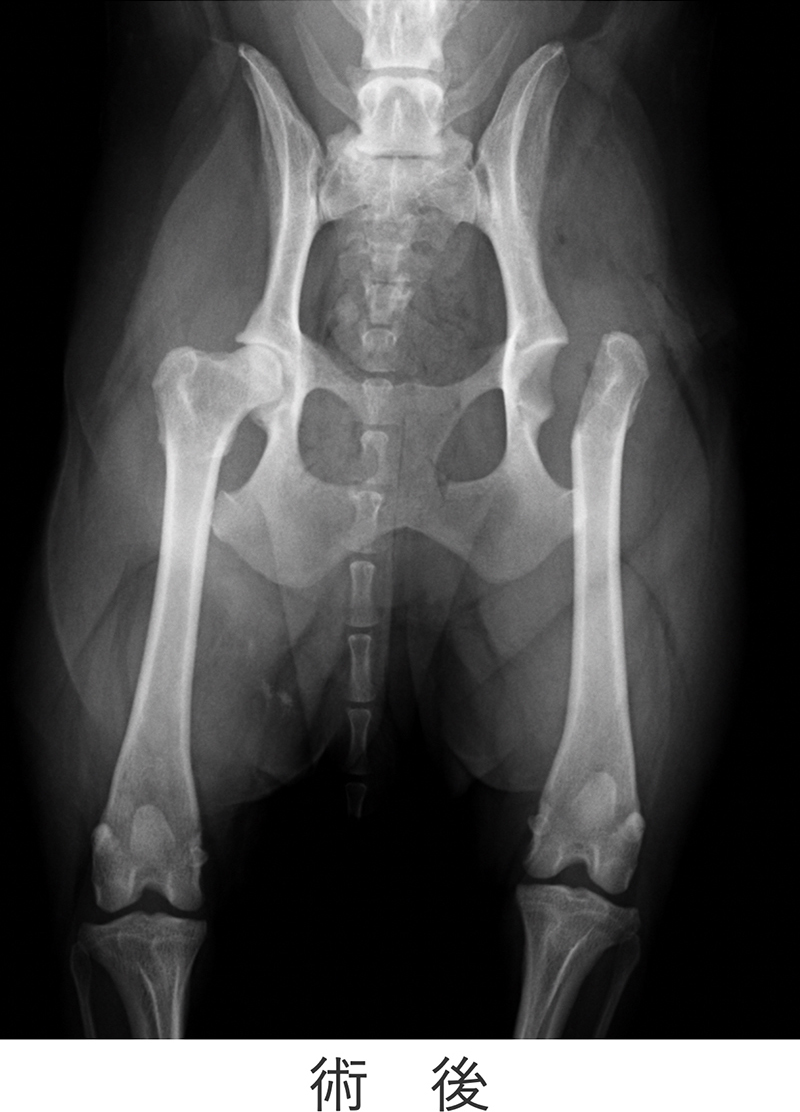

観血的整復術の術後レントゲン画像